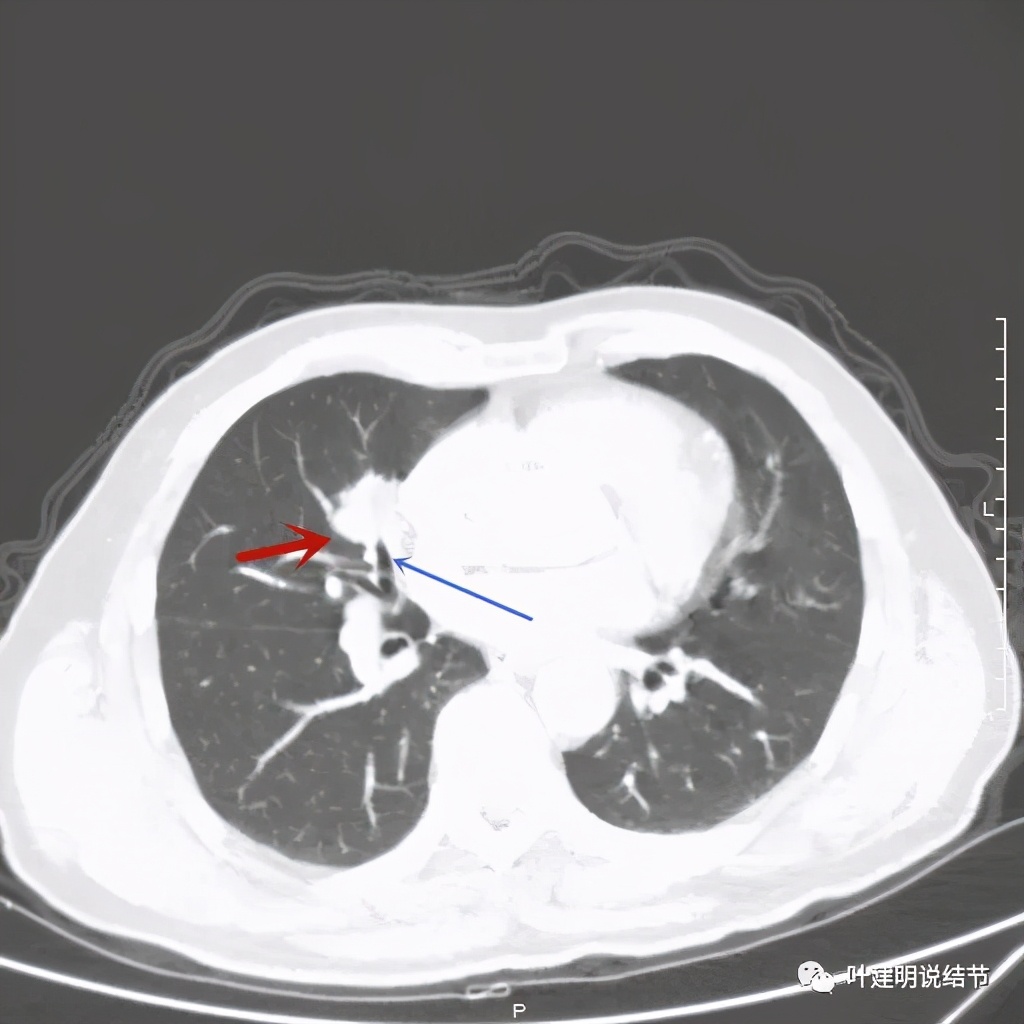

病灶有分叶及胸膜牵拉

以上几图示病灶膨胀感明显,无卫星灶,周围无渗出性改变

上图粉色箭头示细毛刺征,蓝色似支气管截断,红色示病灶膨胀性明显

上图绿色箭头示支气管通气征